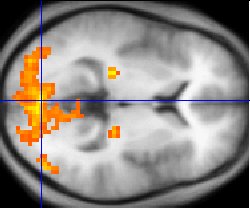

Since the 1980s, sophisticated neuroimaging procedures, such as fMRI (above), have furnished increasing knowledge about the workings of the human brain, shedding light on ancient philosophical problems.

1980年代以降、fMRI(上記)のような高度な神経画像化技術が、人間の脳の働きに関する知見を蓄積し、古くからの哲学的問題に光を当てている。